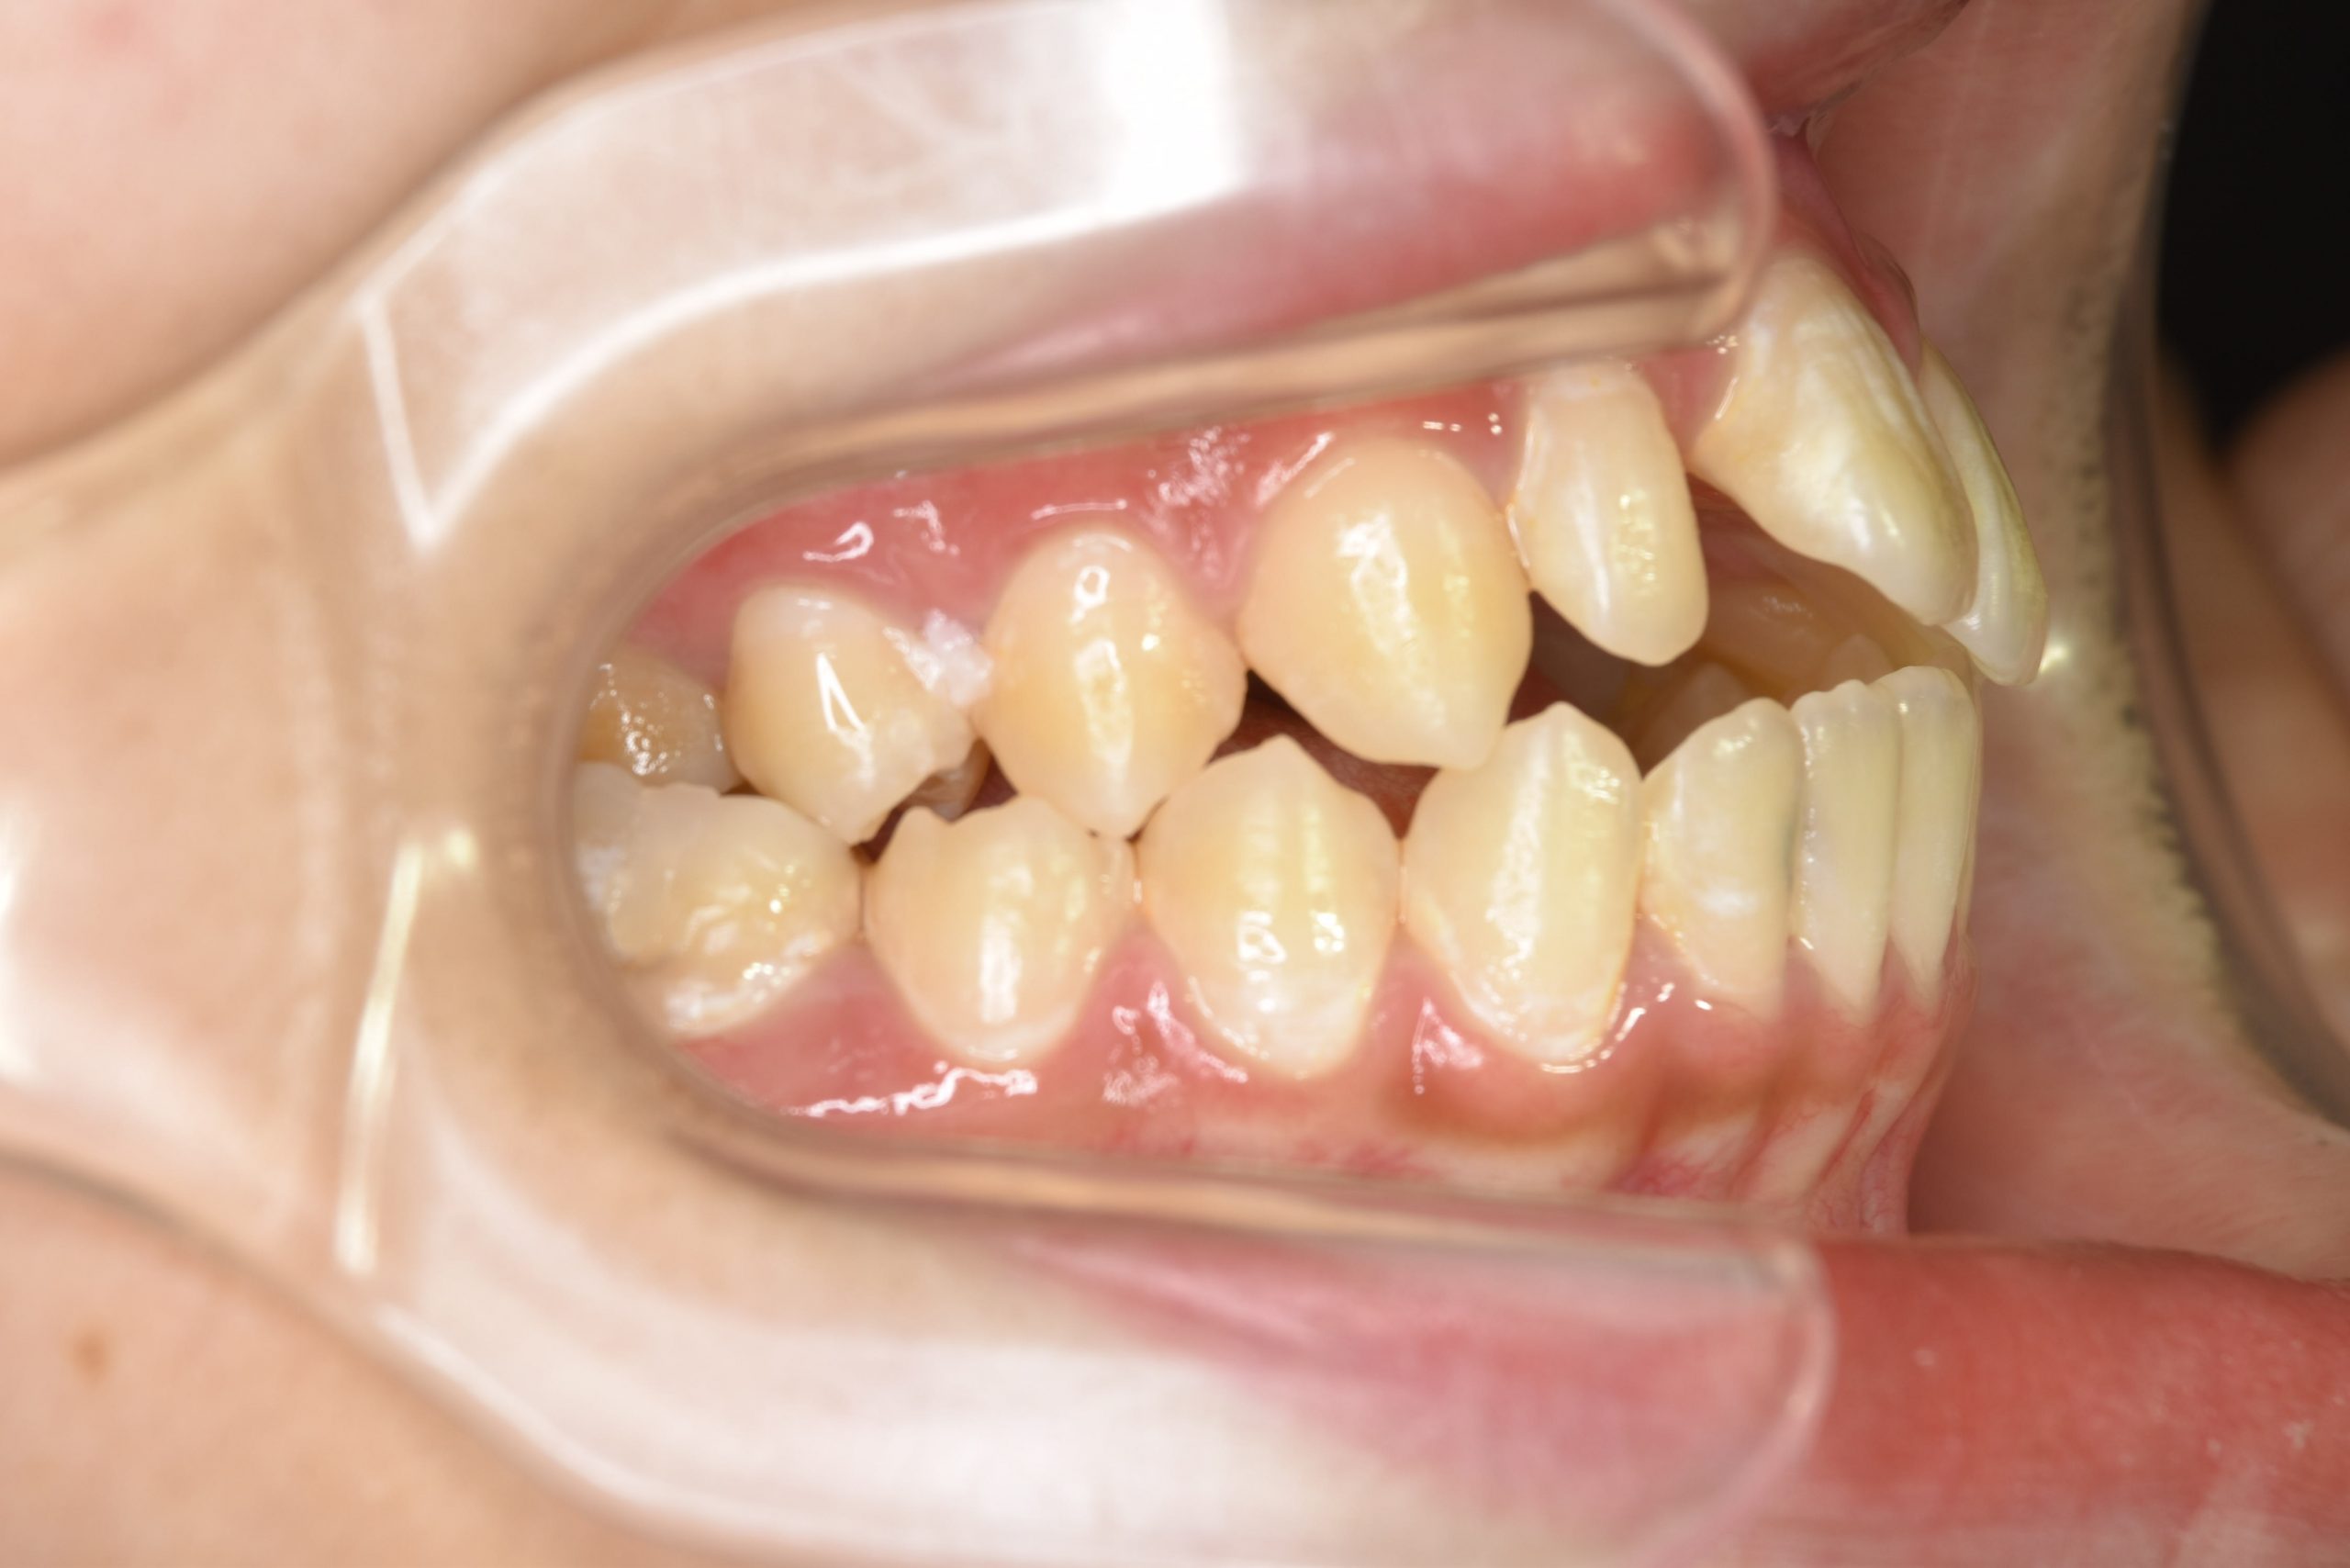

アフター

ワイヤー矯正治療|症例_032

施術内容 MSEと下顎リンガルアーチを用いて上下顎骨を拡大した。

その後マルチブラケット装置を用いて非抜歯で歯牙を配列し良好な咬合を獲得した。

吸指癖と鼻閉症状は改善した。

治癒期間 2年2か月間